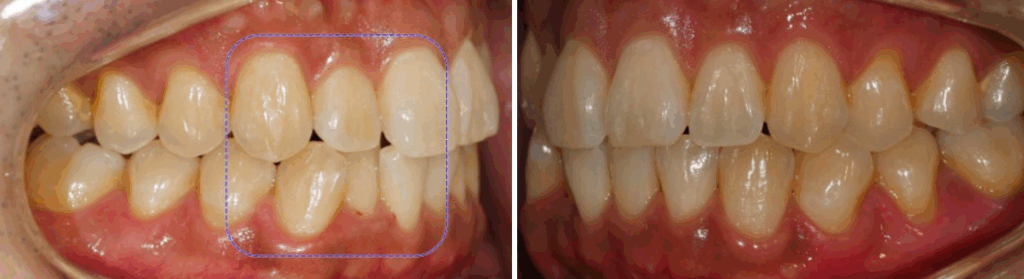

24.03.23

브라켓을 부착한 뒤

정확한 치아 맞물림을 위해

위턱 오른쪽 구치부에 버튼을 부착한 것을

보실 수 있습니다.

24.07.15

이러한 과정 덕분에

치열과 아래 악궁의 형태 개선이 된 것을

확인할 수 있었습니다.

치열이 어느 정도 올곧게 변하면서

치아 사이 공간이 나타난 것을

볼 수 있는데요.

이는 앞서 계획에서 말씀드렸듯이

치아 사이를 삭제하여

미세 조정을 하면서 맞출 수 있습니다.